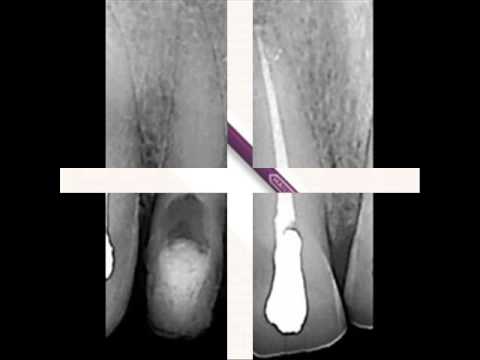

Micro debrider (Микро дебридер) - инструмент для первичной обработки облитерированных или труднопроходимых каналов. Имеет режущие грани Н-файла, длина рабочей части - 16 мм, размеры 20 и 30 (конусность. 02).

Micro-Debrider, эндодонтический ручной инструмент, по ISO тип H-файла

- Тонкая рабочая часть с формой H-файла длиной 7 мм.

- Выпускается в конусности 0,2. Размеры в соответствии с ISO.